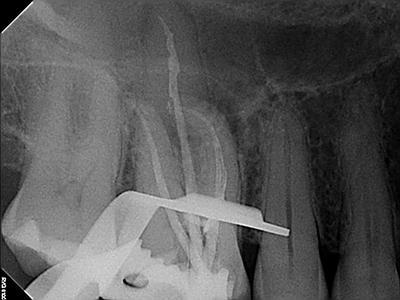

Radiographic Examination:

Tooth # 3 exhibits severe pulpal calcification, periapical radiolucencies associated with all 3 roots and severe dilaceration of the mesiobuccal root.

Conventional non-surgical root canal therapy